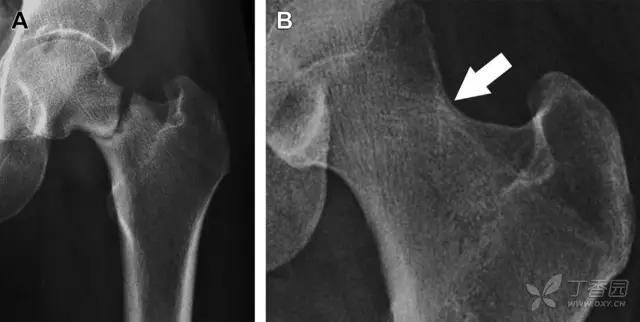

股骨颈骨折常发生在老年人,头下型骨折最常见,但是当股骨外旋或有明显的关节炎骨赘形成时,骨折较难发现。此外,肥胖和骨量减少增加髋部 X 片诊断难度,所以需格外注意。

因骨结构重叠影响,股骨转子骨折发生轻度移位时亦很难发现,加做一个不同角度的 X 线片有助于诊断(图 7)。

图 7 摔倒后股骨大转子骨折。A 正位片初步检查未发现明显骨折,进一步检查发现大转子上方皮质中断(箭头)。B 蛙式侧位片示骨折分离,尤其是后方(箭头)。初步检查时忽视了这一点,是因为股骨颈未能充分显示